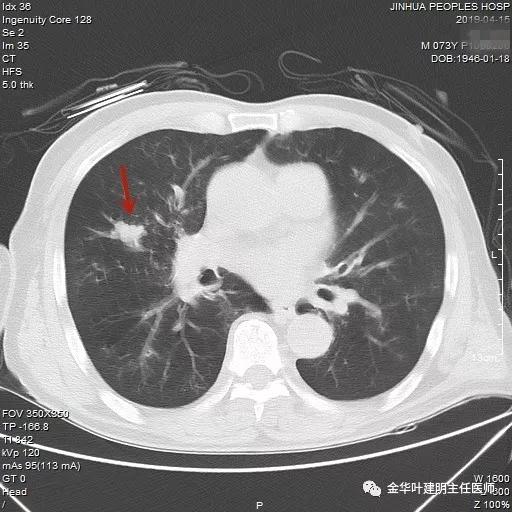

武义的吴某,今年已经73岁了,患有慢性支气管炎与肺气肿多年,每到天气转凉就要胸闷、气急及咳嗽、咳痰发作,严重时还有喘憋症状,每年都要住院1-2次。今年4月份的时候吴某又因慢支急性发作来我院呼吸内科住院。常规检查时发现右肺上叶有一实性结节,约1.5厘米大小,有毛刺及浅分叶,考虑肺癌可能性大,医生建议其行肺穿刺活检。当时图片如下: